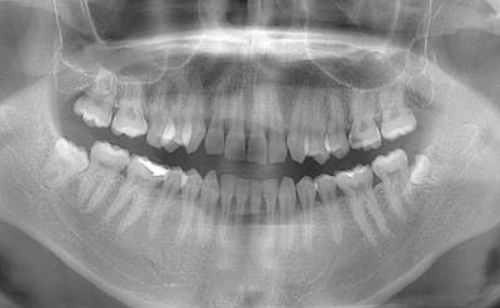

定期検診ではクリーニングのみではなく、経過観察歯のチェックや古くなってきた詰め物・被せ物のチェックなども合わせて行います。1年に1度お口全体のレントゲンをお取りさせて頂き目に見えない虫歯の確認や歯周病による骨吸収の有無をみています。

お口の中の病気はレントゲン写真検査を行わないと診断が難しいものが多くあります。直接見えない部分を把握するためにレントゲン撮影をさせて頂きます。

お口の中の病気はレントゲン写真検査を行わないと診断が難しいものが多くあります。

定期検診の場合約1〜2年に1回ほど、もしくは歯科医師・歯科衛生士の判断で必要な場合撮ることがあります。

| 担当者所見 | ブラッシング指導後、歯石除去を行い定期検診へ移行 矯正治療を行う予定 |

| 特記事項 | 交叉咬合・かみ合わせが強い |

| 担当者所見 | 初診時は歯石が全顎的に付着しており、歯石除去時は出血もありました。特に下の前歯は歯と歯の間を埋めるように多量の歯石が付着していました。ブラッシング指導も行い、定期検診へと移行しました。 定期検診時は全体的な清掃状態も良好で、ご自身も歯ブラシを頑張っているとおっしゃっていました。矯正治療開始後も綺麗で健康な口腔内を維持する為、定期検診を継続的に行っていく予定です。 |